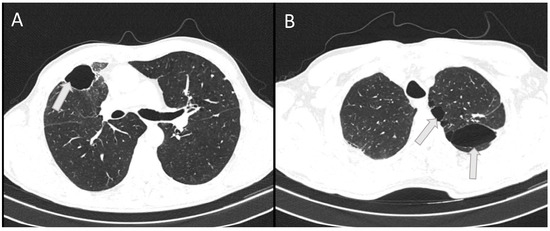

A 53-year-old male patient with no comorbidities, except for being a smoker, without chronic therapy was admitted to the ICU due to severe respiratory failure. Five days before admission, the patient was hit by a metal object on the right side of the chest and complained of shortness of breath. Chest radiography revealed a right-sided pneumothorax, and a thoracic drain was placed (Figure 1A).

Figure 1. Chest radiography on hospital admission with right-sided pneumothorax and a pulmonary infiltrate of the medial and lower lobe of the right lung (A). A complete absence of aeration of the lower and medial right lobe was present on day 3 (B). L: left side.